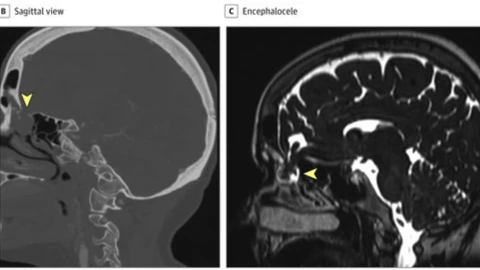

Sin embargo, una tomografía y una resonancia realizadas detectaron una encefalocele, es decir, un revestimiento en el cerebro que se desborda hacia la cavidad nasal, que al insertar el hisopo habría provocada una irritación, lo que causó la fuga de líquido.

La paciente, explica el artículo, fue sometida a una cirugía para corregir la encefalocele, de la cual ya se recupera.